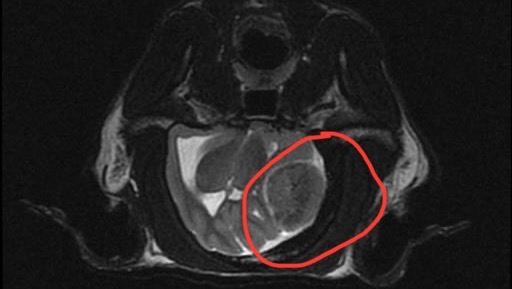

Tabby is only 6 years old. He’s sweet, gentle, and incredibly loving — my little shadow and my best friend. He is my life. A few weeks ago, everything changed. Tabby began walking low to the ground, like he was in pain or afraid. He barely slept. Then he suddenly stopped drinking water, and within a short time, he also stopped peeing and pooping. After visiting multiple ER, spending 3 days in the hospital with a catheter, and doing countless tests, we finally did an MRI - and they found a brain tumor.

His condition is worsening. He’s struggling to use the toilet and move normally. He sleeps most of the day and doesn’t play like he used to. The tumor is pressing on his brain. Steroid treatment gave us a few days of hope, but the relief didn’t last.